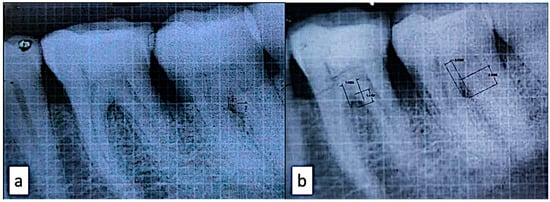

3.7. Bone Area Fill